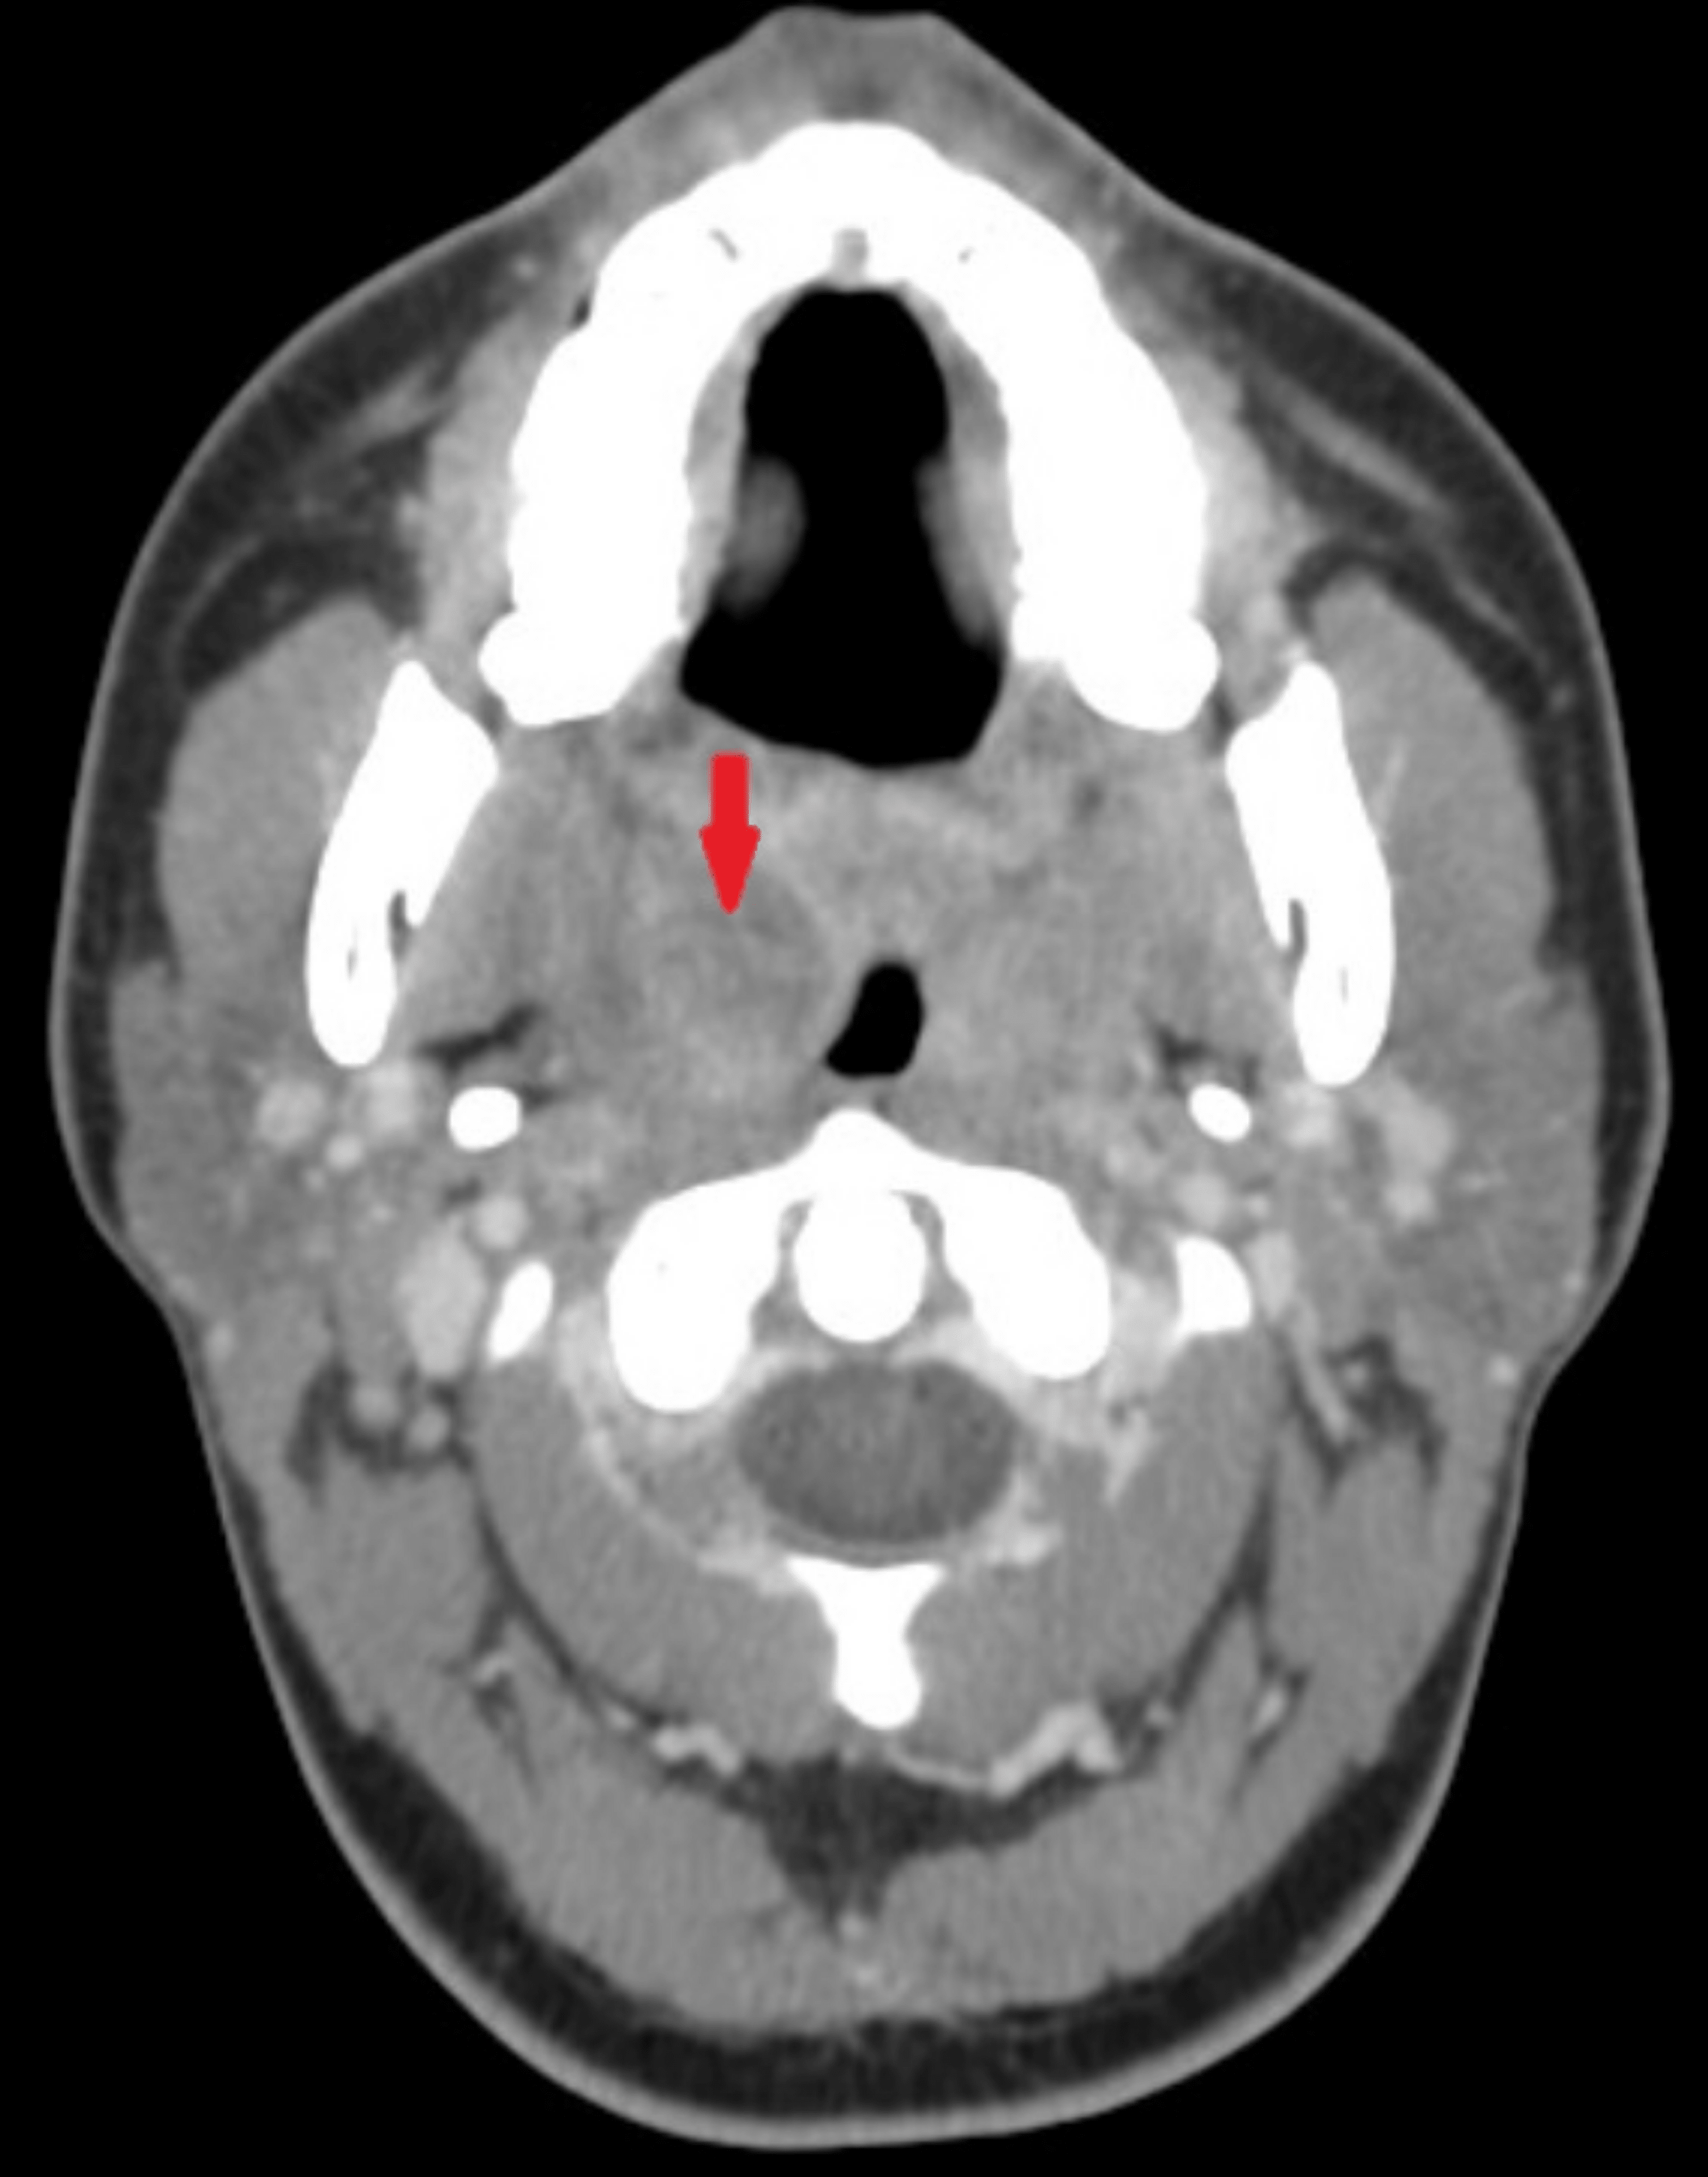

Cureus Are Computed Tomography Scans Necessary for the Diagnosis of Peritonsillar Abscess? Abscess Vs Phlegmon an alternate term for cellulitis is phlegmon. differentiate between various deep neck infections based on anatomical location and clinical presentation. phlegmon is an area of soft tissue or fluid density effacing or displacing usual fat or other connective tissue and. A phlegmon is unbounded and can keep spreading out. Instead the infection spreads along tissue. the. Abscess Vs Phlegmon.

From radiopaedia.org

Image Abscess Vs Phlegmon Instead the infection spreads along tissue. phlegmon is an area of soft tissue or fluid density effacing or displacing usual fat or other connective tissue and. A phlegmon is unbounded and can keep spreading out. differentiate between various deep neck infections based on anatomical location and clinical presentation. a phlegmon results when an acute infection is not. Abscess Vs Phlegmon.